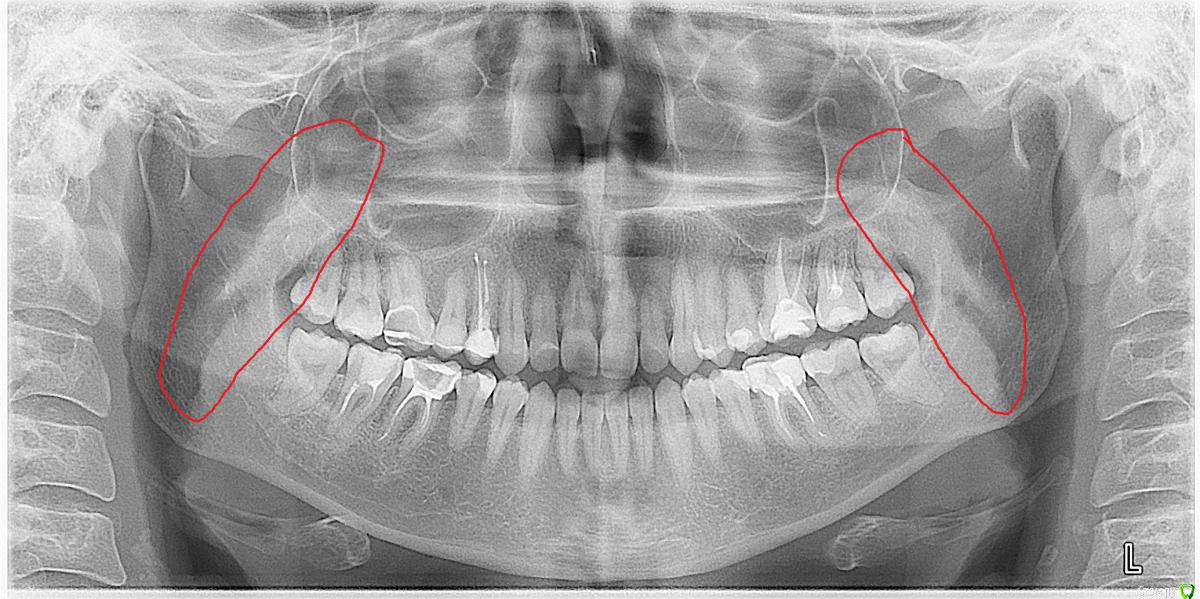

После лечения жевательных зубов на нижней и верхней челюсти начался дискомфорт в прикусе. Врач подшлифовал пломбы, начались боли в мышцах. Попробывал завысить, стало еще хуже. Через месяц начались щелчки с левой стороны, боли усиливались в районе жевательных мышц. Пробывали капы, результатов не давало. Сейчас не могу ни переживать толком еду, спать вообще не удобно. челюсть в обычном положении зафиксировать не могу, жевательных мышц совсем не чувсвую,разговаривать тоже не удобно, слюну ковтать трудно.Сильно напряжены мышцы возле носа, сзади головы и шеи, раслабить никак не могу. Начались сильные головные боли, боли в шее, в левой лопатке.  Сделали мрт шейного отдела, показало деформация шейного отдела и грыжи. Стоматологи говорят что это из-за прикуса. К кому обратиться помогите,Есть фотография до лечения, прикрепляю.

КТ даёт лишь информацию относительно костных структур сустава, а хотелось бы увидеть что там со связками, но для этого нужно МРТ. Со стороны костных структур я не увидел каких-то критических изменений, за исключением может быть ремоделирования суставных поверхностей.